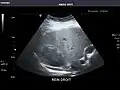

Aorta: Visualized portions normal in caliber, 16 x 15 mm.

Aorta -